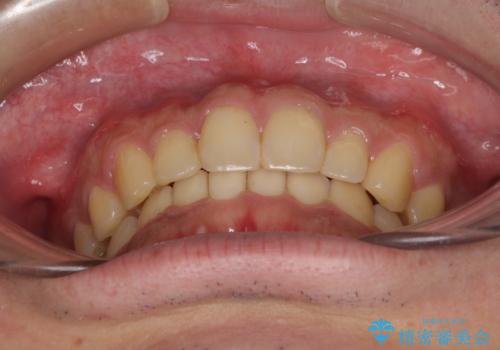

- 上下前歯のデコボコと下の前歯が隠れるほどの深い咬み合わせを気にして来院された患者様です。

インビザラインによる上下歯列の拡大と、IPR(歯と歯の間を削る)にるスペースの獲得により、口元のデコボコとディープバイトを改善することとしました。

デコボコがなくなったことで日頃の清掃が行いやすくなり、深い咬み合わせが改善したことで、食いしばりによる顎の負担も軽減されました。